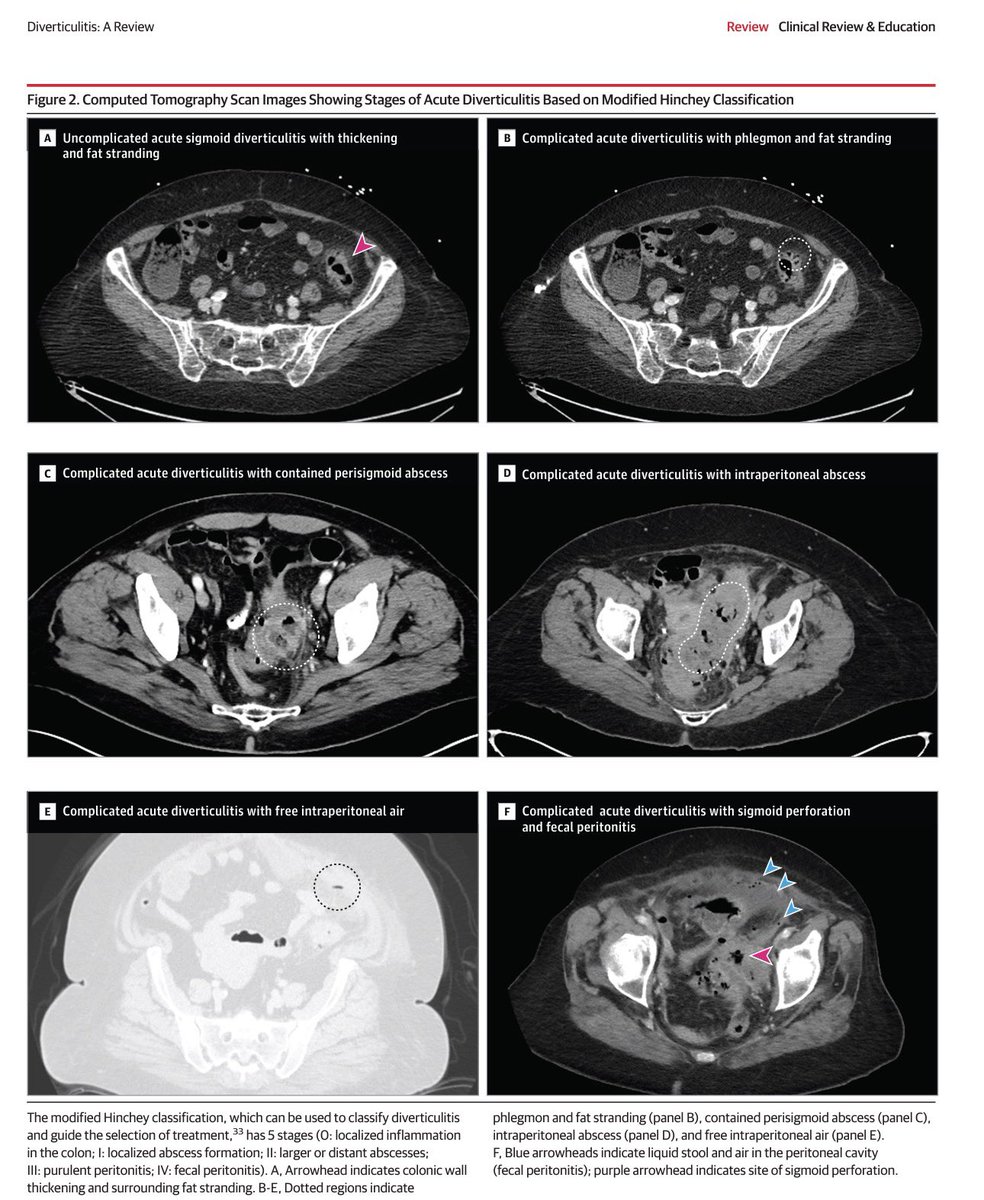

✅“Diverticulitis: A Review” (JAMA, 2025) revisa la evidencia más reciente sobre epidemiología, diagnóstico y manejo de la diverticulitis. 📌 Puntos clave: 1️⃣. Epidemiología La diverticulitis tiene una incidencia anual de 180 por 100 000 personas y causa ≈200.000